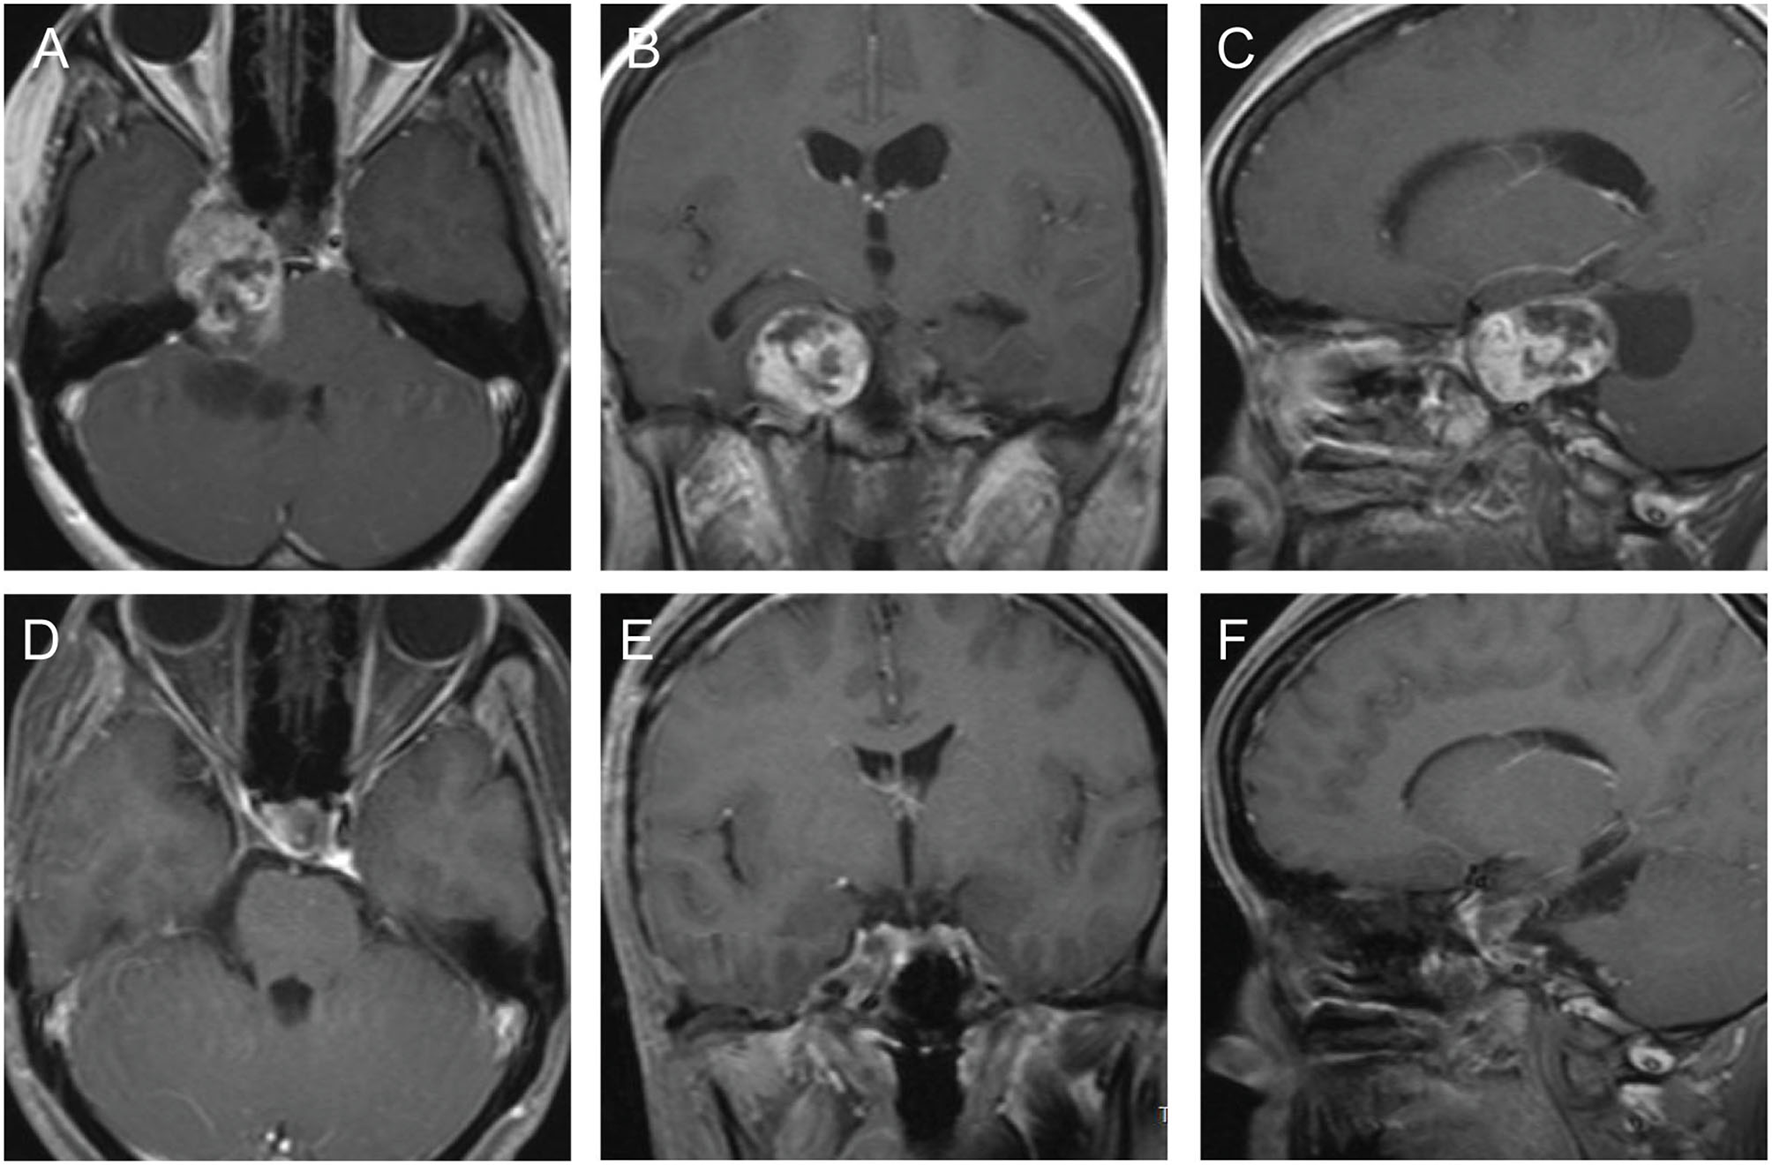

A 30-year old female patient, her clinical symptoms included Hypometropia, amenorrhea, and lactation. Eight months ago, this patient underwent an operation via microscopic transnasal transsphenoidal approach and partial tumor remained and treated by gamma knife. However, the residual tumor progressed during the follow-up, MRI study showed a mass with equal T1 and equal T2 signal within slice shot T1 signal, located in the right CS. Enhanced MRI showed the enhancement of tumor is Heterogeneous (Figures 1A–C). Then the patient underwent microscopic surgery via pretemporal transcavernous approach using FT craniotomy. The tumor was gross total removed extradurally (Figures 1D–F). After the surgery, the patient did not suffer any surgery-related complications. The postoperative diagnosis was chondroma.

Figure 1

The preoperative and postoperative MRI imaging of case 1. (A–C) Preoperative MRI showed the tumor involved intrasellar and the right CS. (D–F) Postoperative MRI showed the tumor was gross total resected.